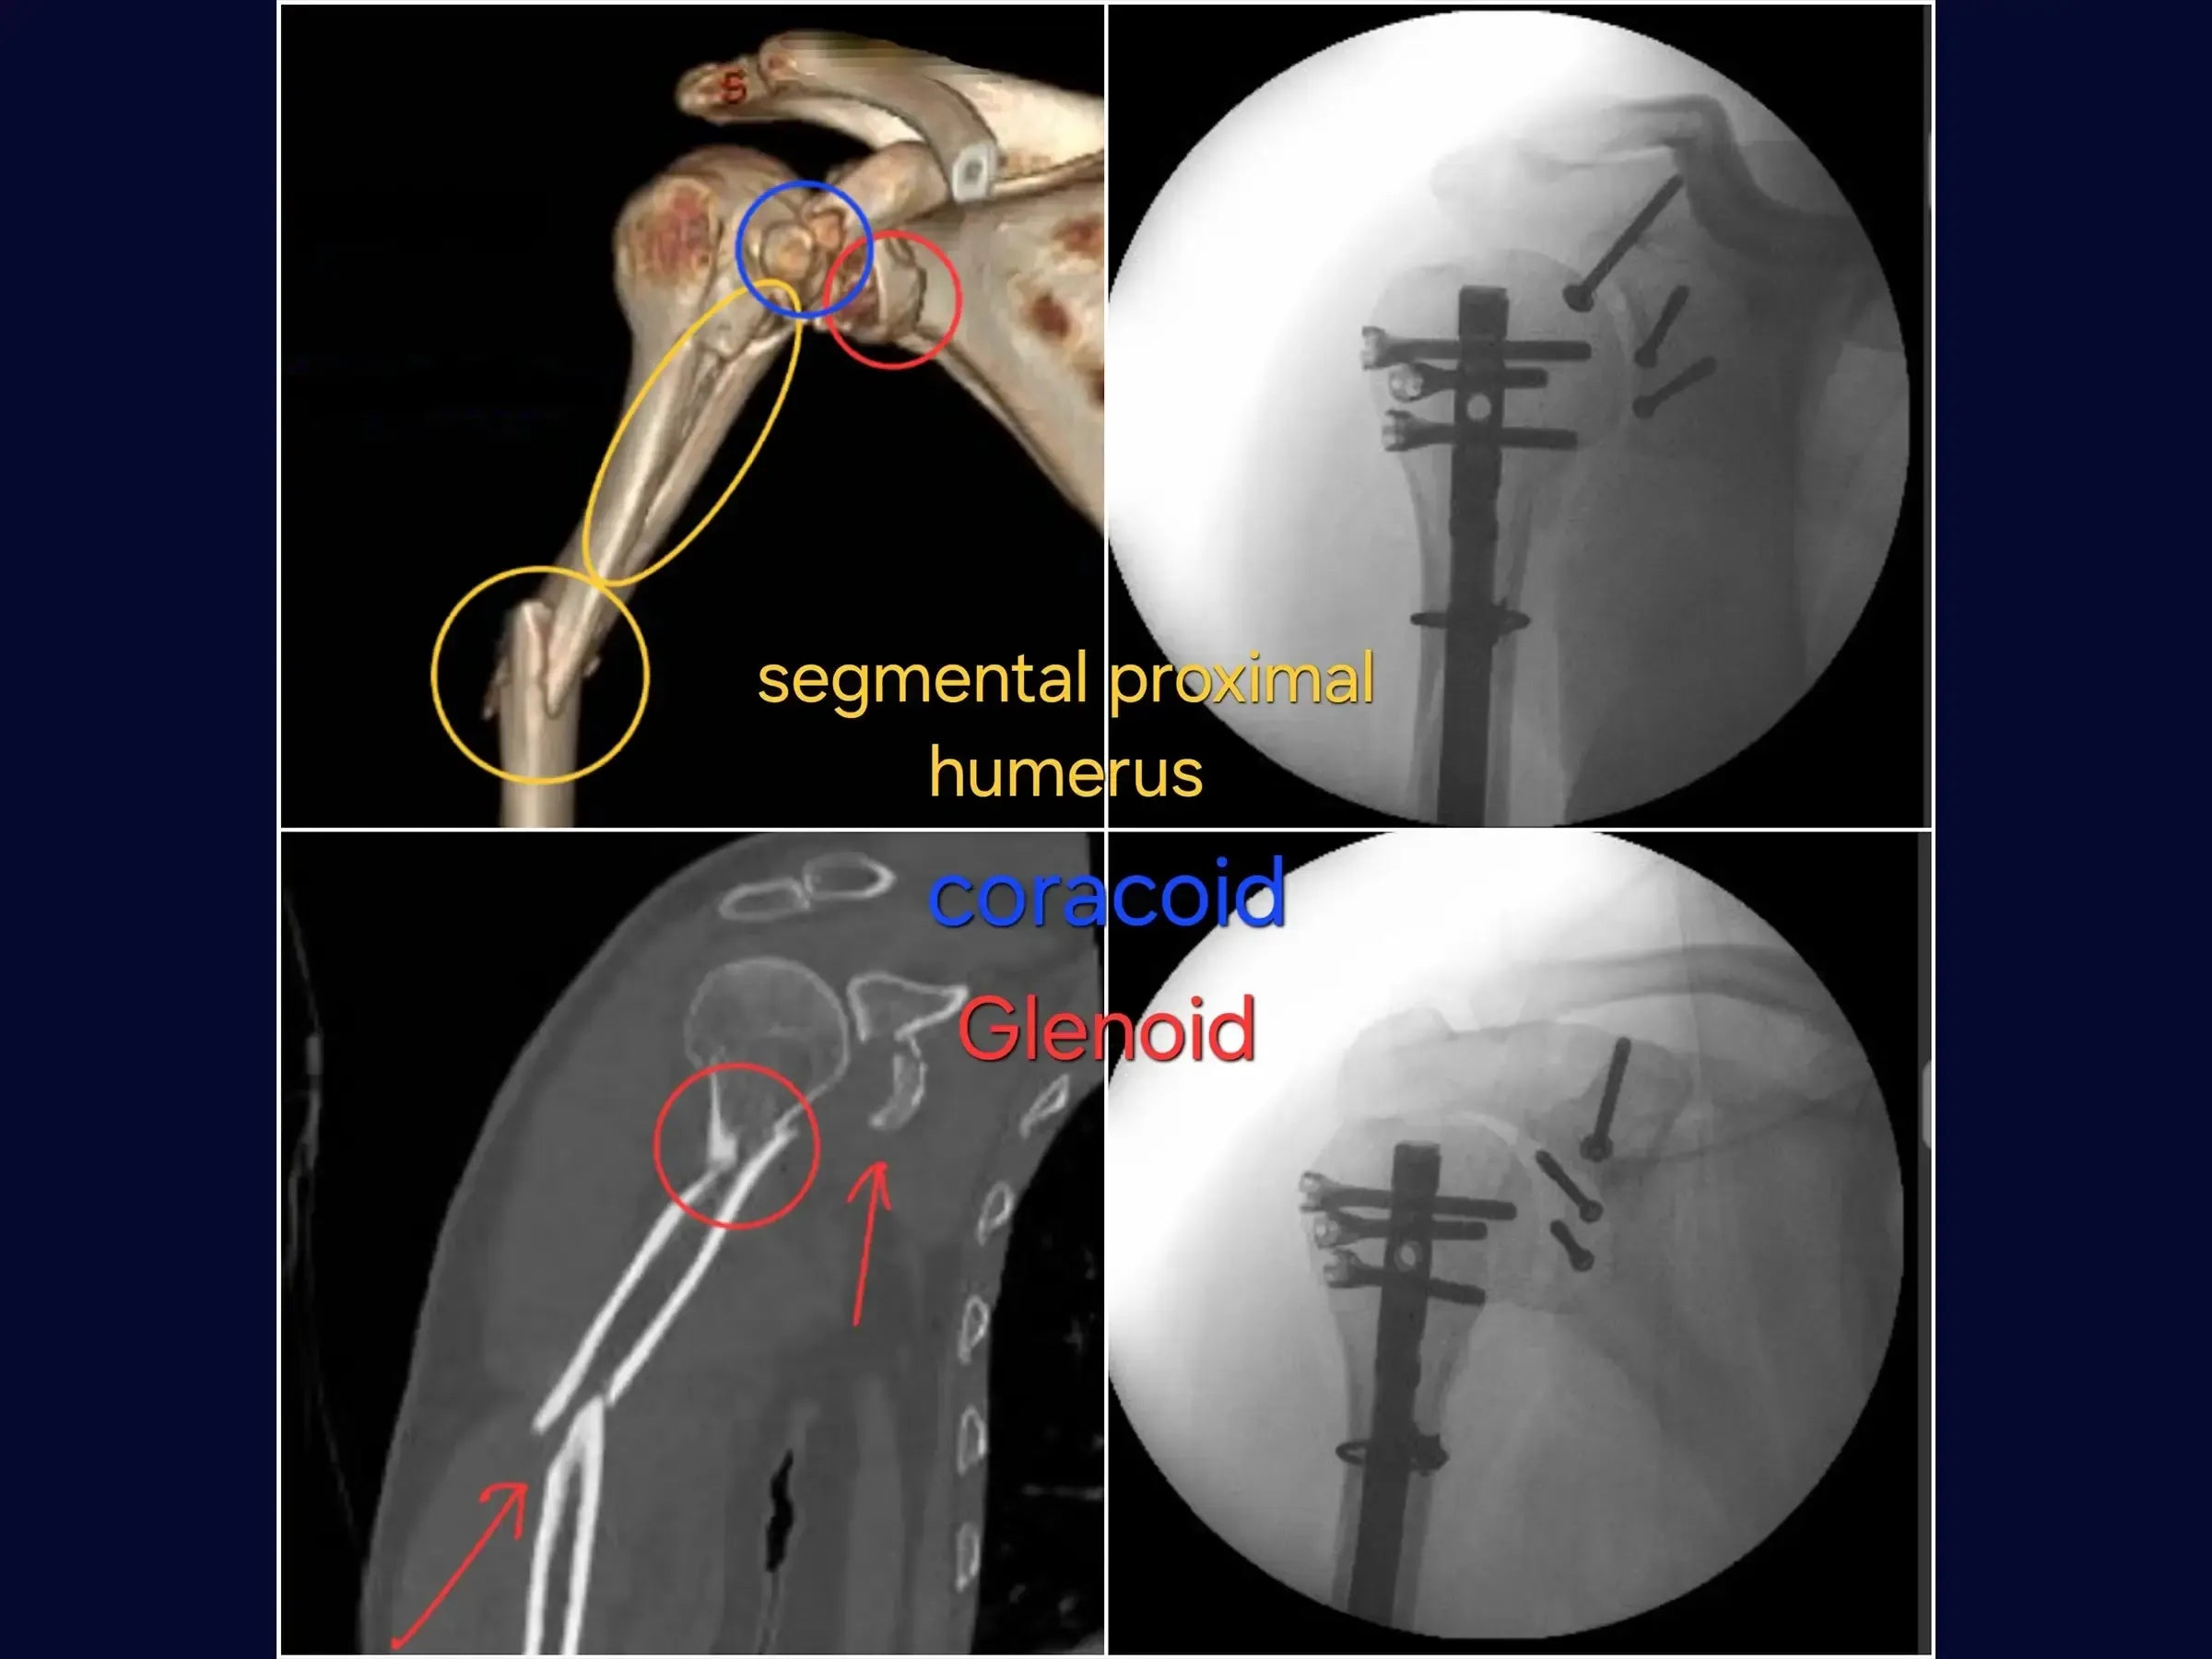

Fratura Segmentar do Úmero Associada a Fraturas da Glenoide e Processo Coracoide

- Manejo cirúrgico de fratura segmentar do úmero.

- Fixação de fratura da borda anterior da glenoide.

- Estabilização de fratura do processo coracoide.

- Osteossíntese com haste intramedular e cerclagem no úmero.

- Fixação com parafusos na glenoide e coracoide.

- Reconstrução Segmentar do Úmero: Abordagem sistemática para identificação dos vértices da fratura, redução do segmento proximal e fixação com haste intramedular e parafusos proximais, complementada por cerclagem, para estabilidade e restauração anatômica.

- Fixação Precisa da Glenoide: Técnica de incisão e separação do subescapular da cápsula articular para exposição e redução do fragmento da glenoide, com inserção de fios guia e parafusos para assegurar a congruência articular e estabilidade.

- Estabilização do Coracoide: Demonstração da fixação do processo coracoide, preso ao tendão conjunto, com parafuso de compressão.